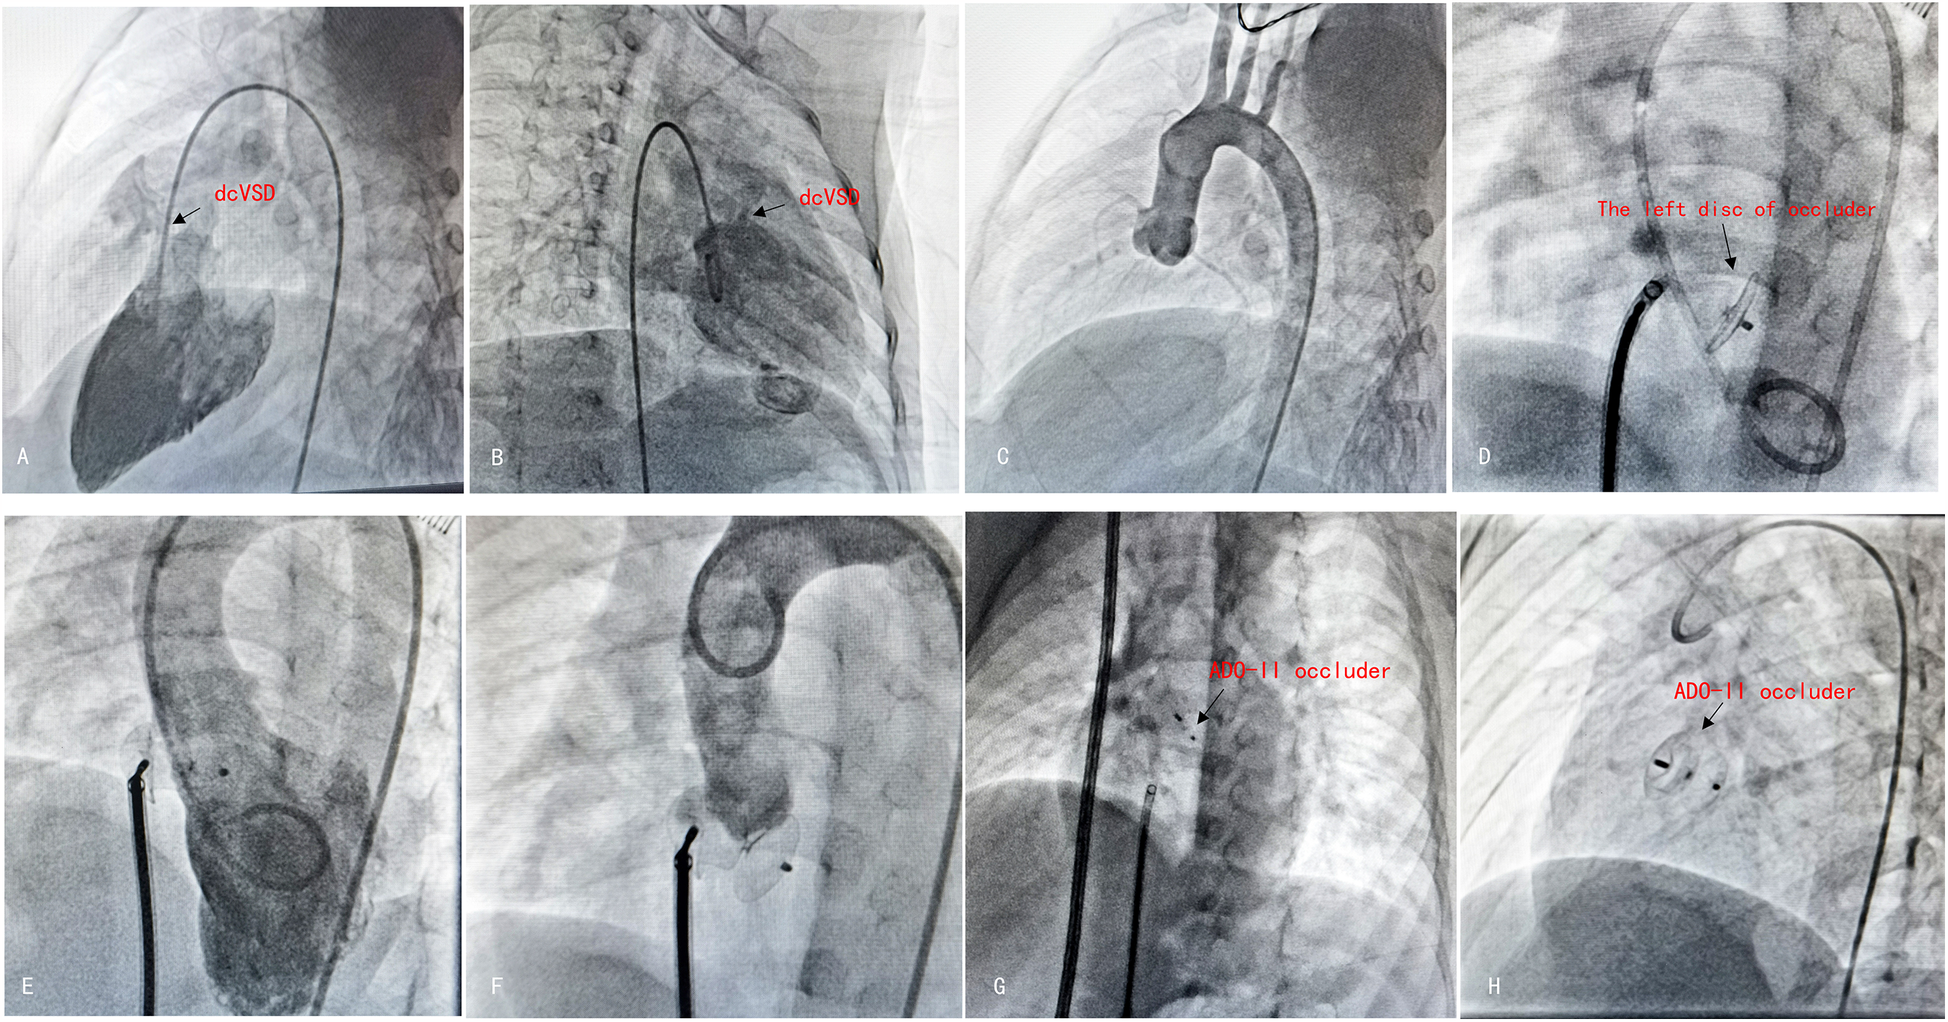

Figure 3

The procedure of antegrade dcVSD closure. (A,B) Left ventricular angiography was performed to confirm the position and size of dcVSD from two different angles—left anterior oblique at 60°cranial 20° (A) and right anterior oblique at 20° (B). (C) Ascending aortogram was performed to observe for AR and AVP. (D) After establishing the delivery pathway, the left disc was deployed at the appropriate position. (E,F) Left ventricular and aortic angiography were repeated to confirm the absence of RS and no exacerbation of AR. (G) Released the right disc. (H) A final radiograph was taken to confirm the occluder's position.

The interventional group typically employed transthoracic echocardiography for continuous intraoperative cardiac monitoring. The treatment was performed under general anesthesia, a 5F/6F/7F arterial and venous sheath was placed, and heparin (100 U/kg) was injected for anticoagulation. Using a guidewire through the femoral vein, the delivery system was progressed sequentially into the right femoral vein, inferior vena cava, right atrium, right ventricle, and across the VSD into the left ventricle. Pressure curves were recorded, and blood flow was calculated. During the procedure, left ventricular and aortic angiography was conducted using at a left oblique projection at 90°/cranial tilt of 20° (or right oblique at 30°/cranial tilt of 20°) to examine the VSD shunt and the condition of the aortic valve. Under fluoroscopic guidance, the delivery sheath was pushed through the VSD into the left ventricle, and an appropriately sized occluder was selected based on preoperative ultrasonography and angiographic data. After deploying the occluder, angiography and intraoperative echocardiography were used to confirm the appropriate position of the device, absence of residual shunting, unobstructed outflow tracts of the left and right ventricles, and normal valve function. The sheath was subsequently removed, and hemostasis was established by compression. Postoperatively, dexamethasone was provided intravenously for 3–5 days (Figures 2, 3).